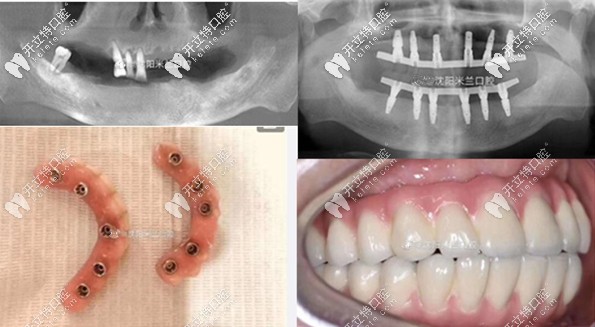

沈陽米蘭口腔全口種植牙案例

沈陽米蘭口腔種植牙案例賞析

張叔缺牙10多年了,慕名來到沈陽米蘭口腔,采用方式:全口種植即刻戴牙,當(dāng)天種牙當(dāng)天用牙,種完后非常滿意,開心的像個孩子。

沈陽米蘭口腔種植牙采用,三維設(shè)計軟件規(guī)劃植體,設(shè)計并生成數(shù)字化種植導(dǎo)板,當(dāng)天種植當(dāng)天用。